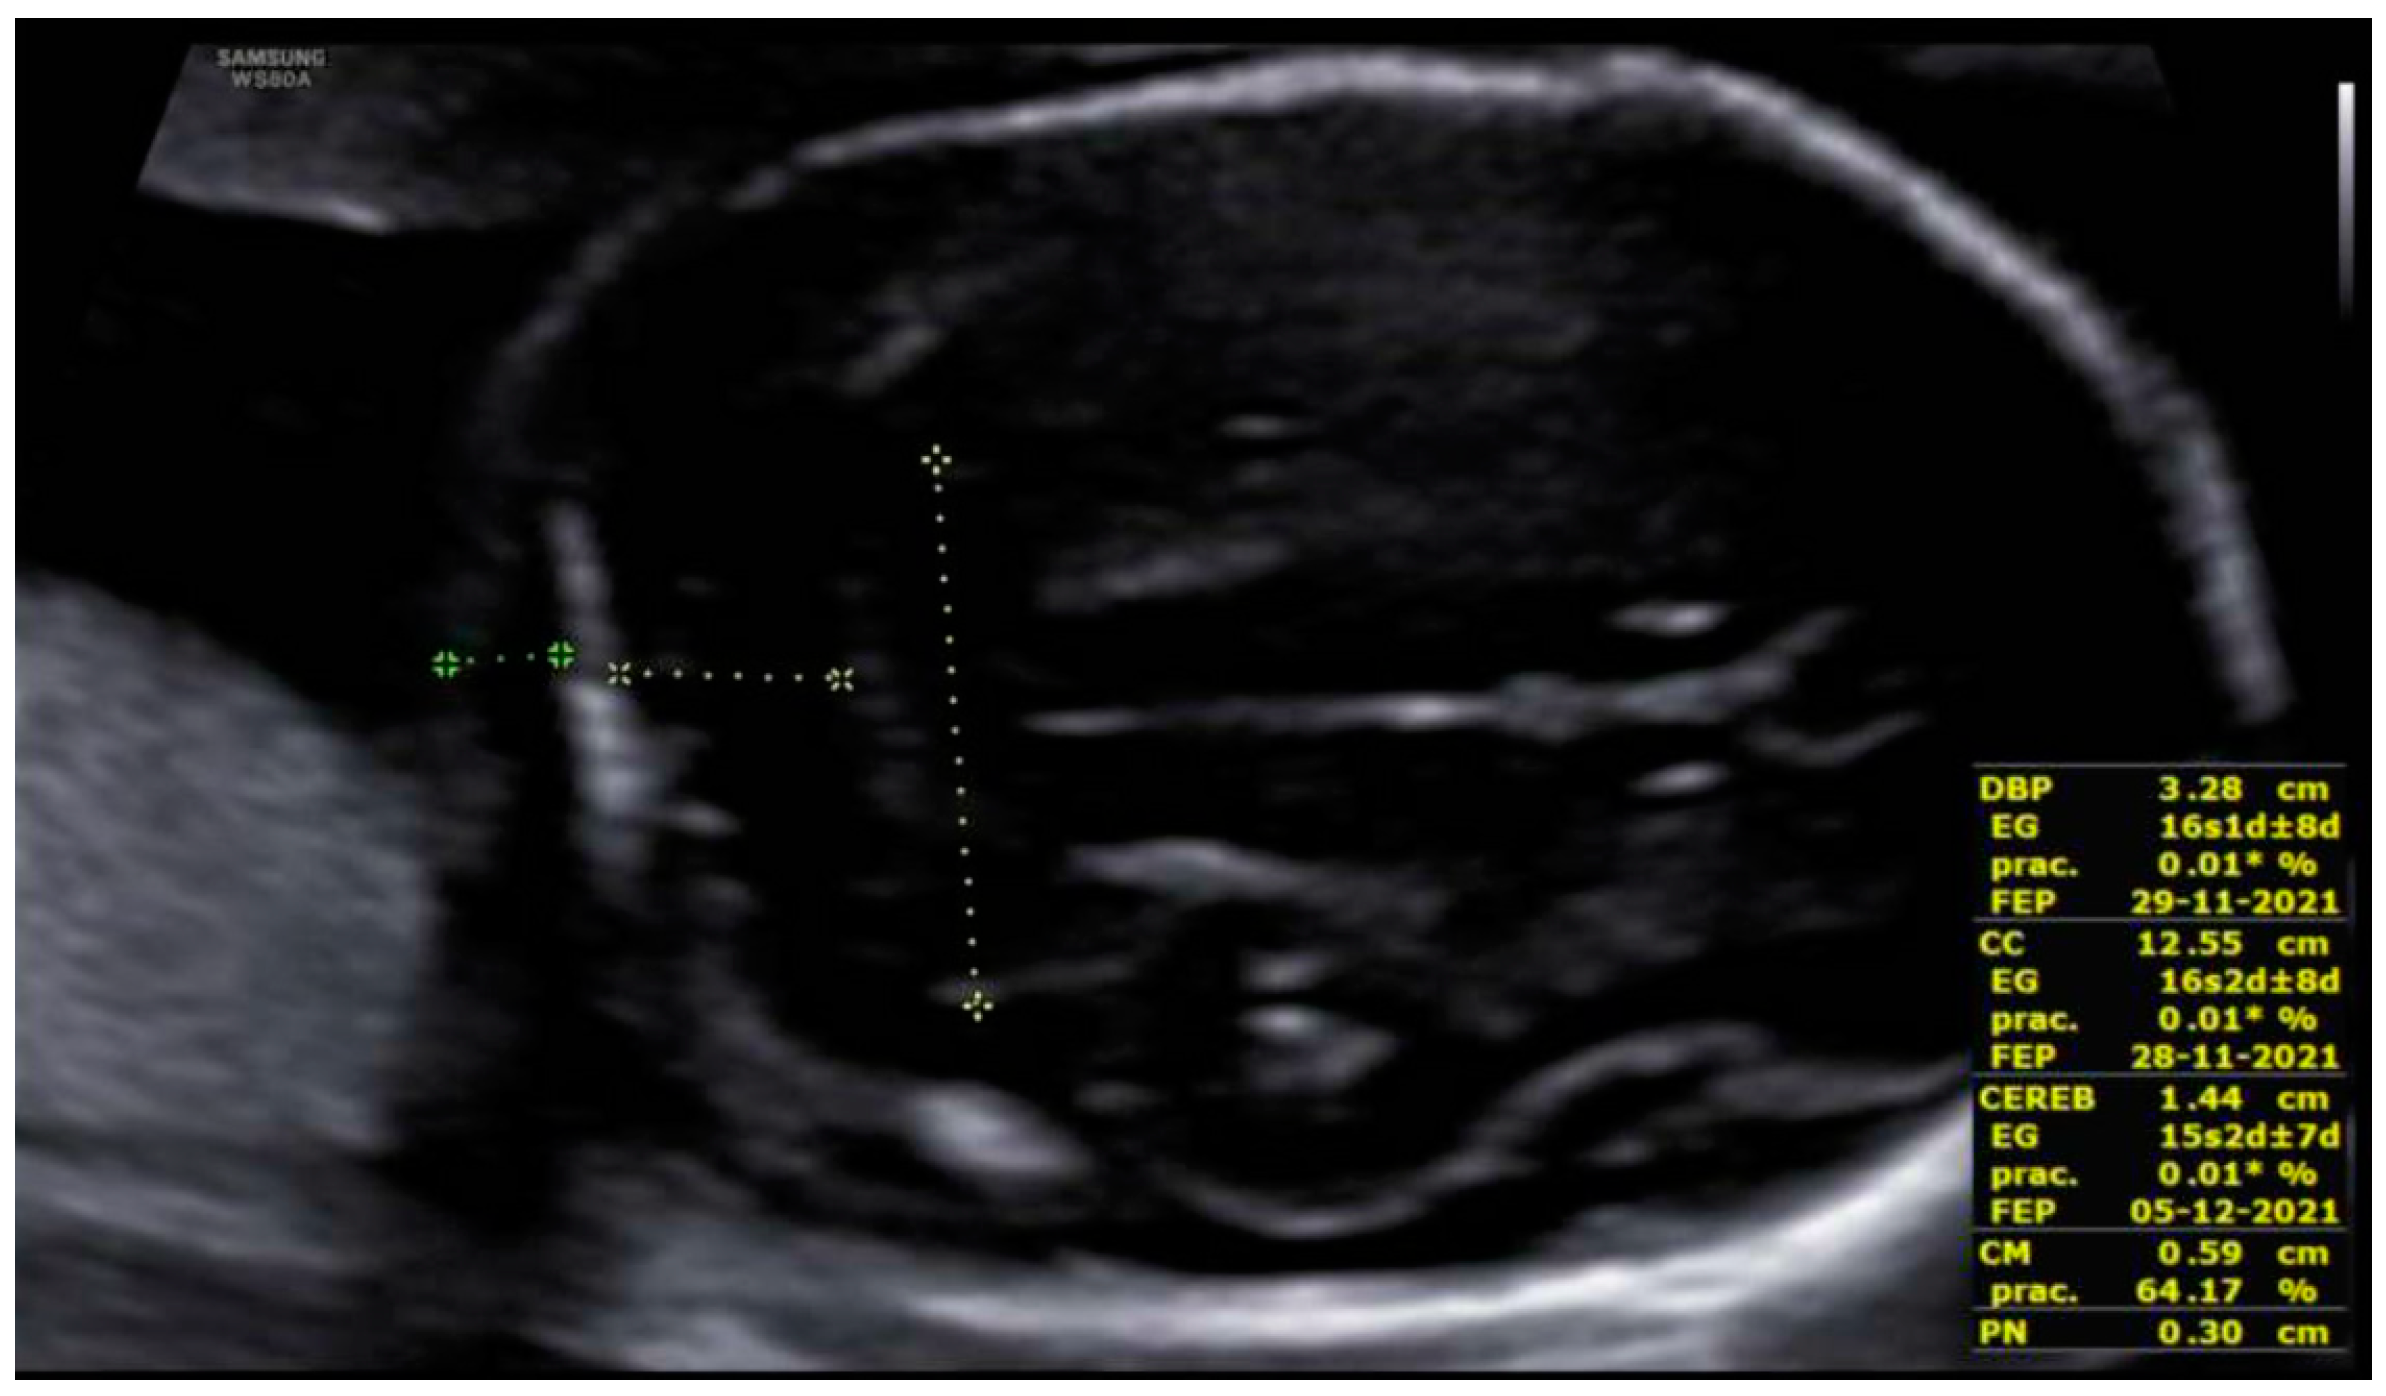

3. Results: Case Presentation

| Microcephaly | 85% | Yes | No |

| Agenesis/hypoplasia of CC | 36% | Yes | No |